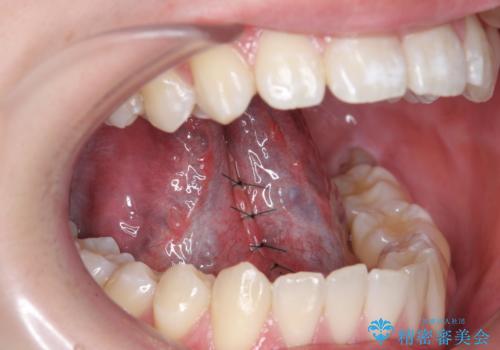

- 舌が動かしにくく、発音に支障があるため、舌小帯切除術を希望された方の症例です。

舌小帯は舌の下にある線維性のスジです。これが短かったり、強直していると、舌運動を上手く行えず、発音や咀嚼・嚥下等に弊害をきたす場合があります。

舌小帯を切除することで舌の可動域が広がり、上記の弊害を改善することが可能です。